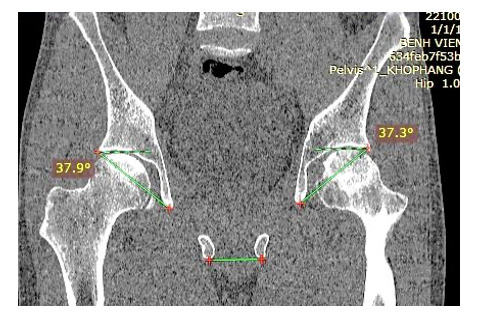

The acetabular anteversion angle was measured on the axial plane as the angle formed by the line connecting the anterior and posterior edges of the acetabulum with the line perpendicular to the line connecting the two ischial tuberosities (Image 3). The acetabular inclination angle was determined on the coronal plane as the angle formed by the line connecting the superior outer edge of the acetabulum and the “tear drop” with the horizontal line passing through the two ischial tuberosities (Image 4).